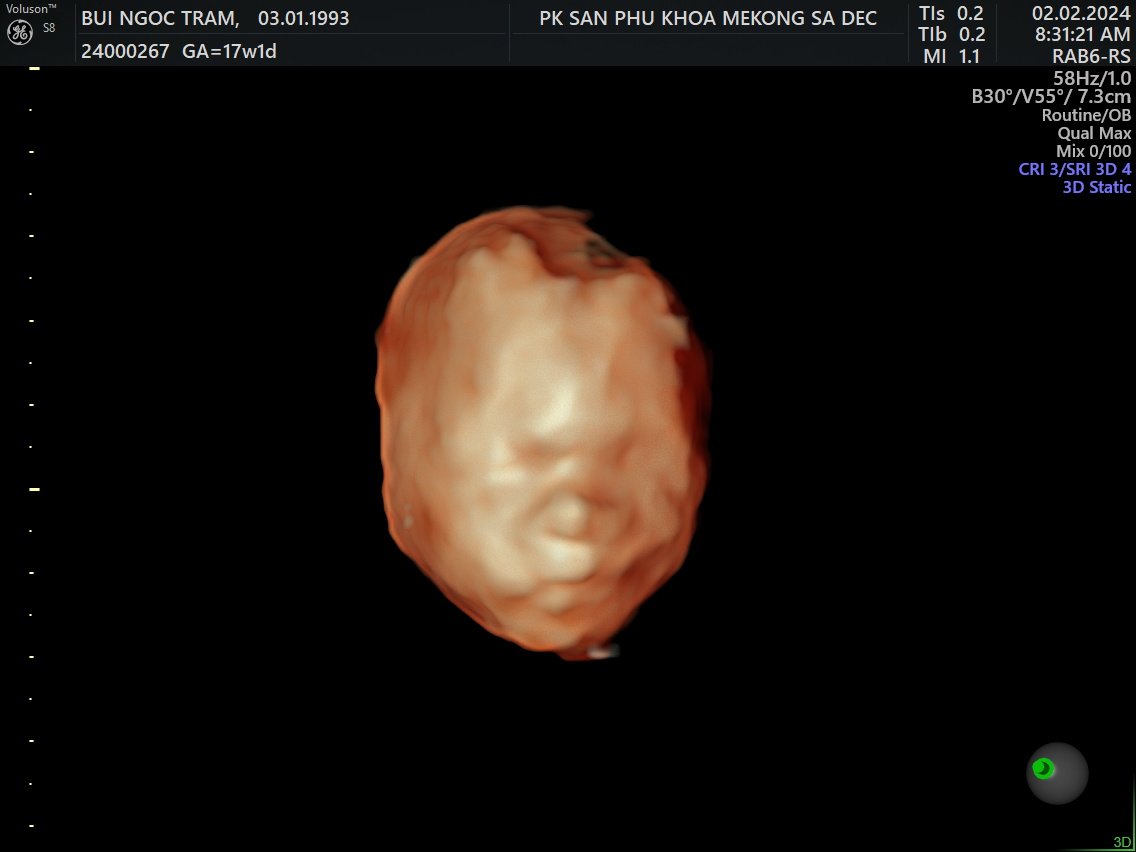

5. Siêu âm 5D

Tuần 17

2 Feb 2024

Về Sadec, được đi siêu âm 5D

Là con trai, hơi ú và hành mẹ bị viêm bạch huyết, hên là phát hiện sớm và được bác sĩ cho thuốc!